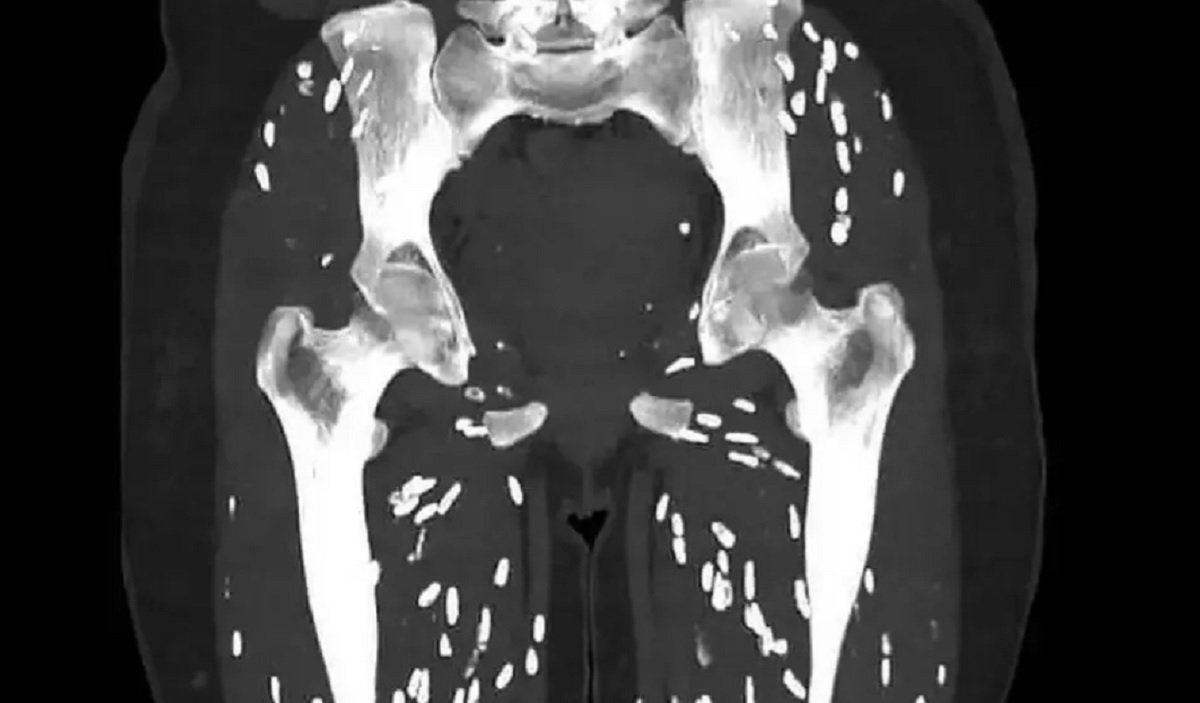

Riauaktual.com - Seorang dokter baru-baru ini membagikan hasil Computed Tomography Scan (CT Scan) yang mengerikan. CT Scan tersebut menunjukkan kondisi kaki pasien setelah mengonsumsi daging babi setengah matang. Tentunya kondisi ini menjadi pengingat akan pentingnya untuk memanggang daging babi hingga benar-benar matang.

Dokter Sam Ghali, yang memiliki lebih dari 630 ribu pengikut di X, membagikan foto hasil CT scan tersebut dan meminta pengikutnya menebak diagnosisnya. Dia menggambarkan gambar itu sebagai salah satu CT scan paling gila yang pernah dia lihat.

Setelah memberi waktu 24 jam untuk menebak, dr. Ghali mengungkapkan bahwa pasien tersebut menderita Sistiserkosis. Infeksi ini disebabkan oleh konsumsi kista larva Taenia solium, juga dikenal sebagai Cacing Babi.

CT scan yang dibagikan menunjukkan respons inflamasi tubuh terhadap sistiserkosis, yang membunuh larva dan menyebabkan kalsifikasi, dikenal sebagai kalsifikasi butiran beras karena penampilannya.